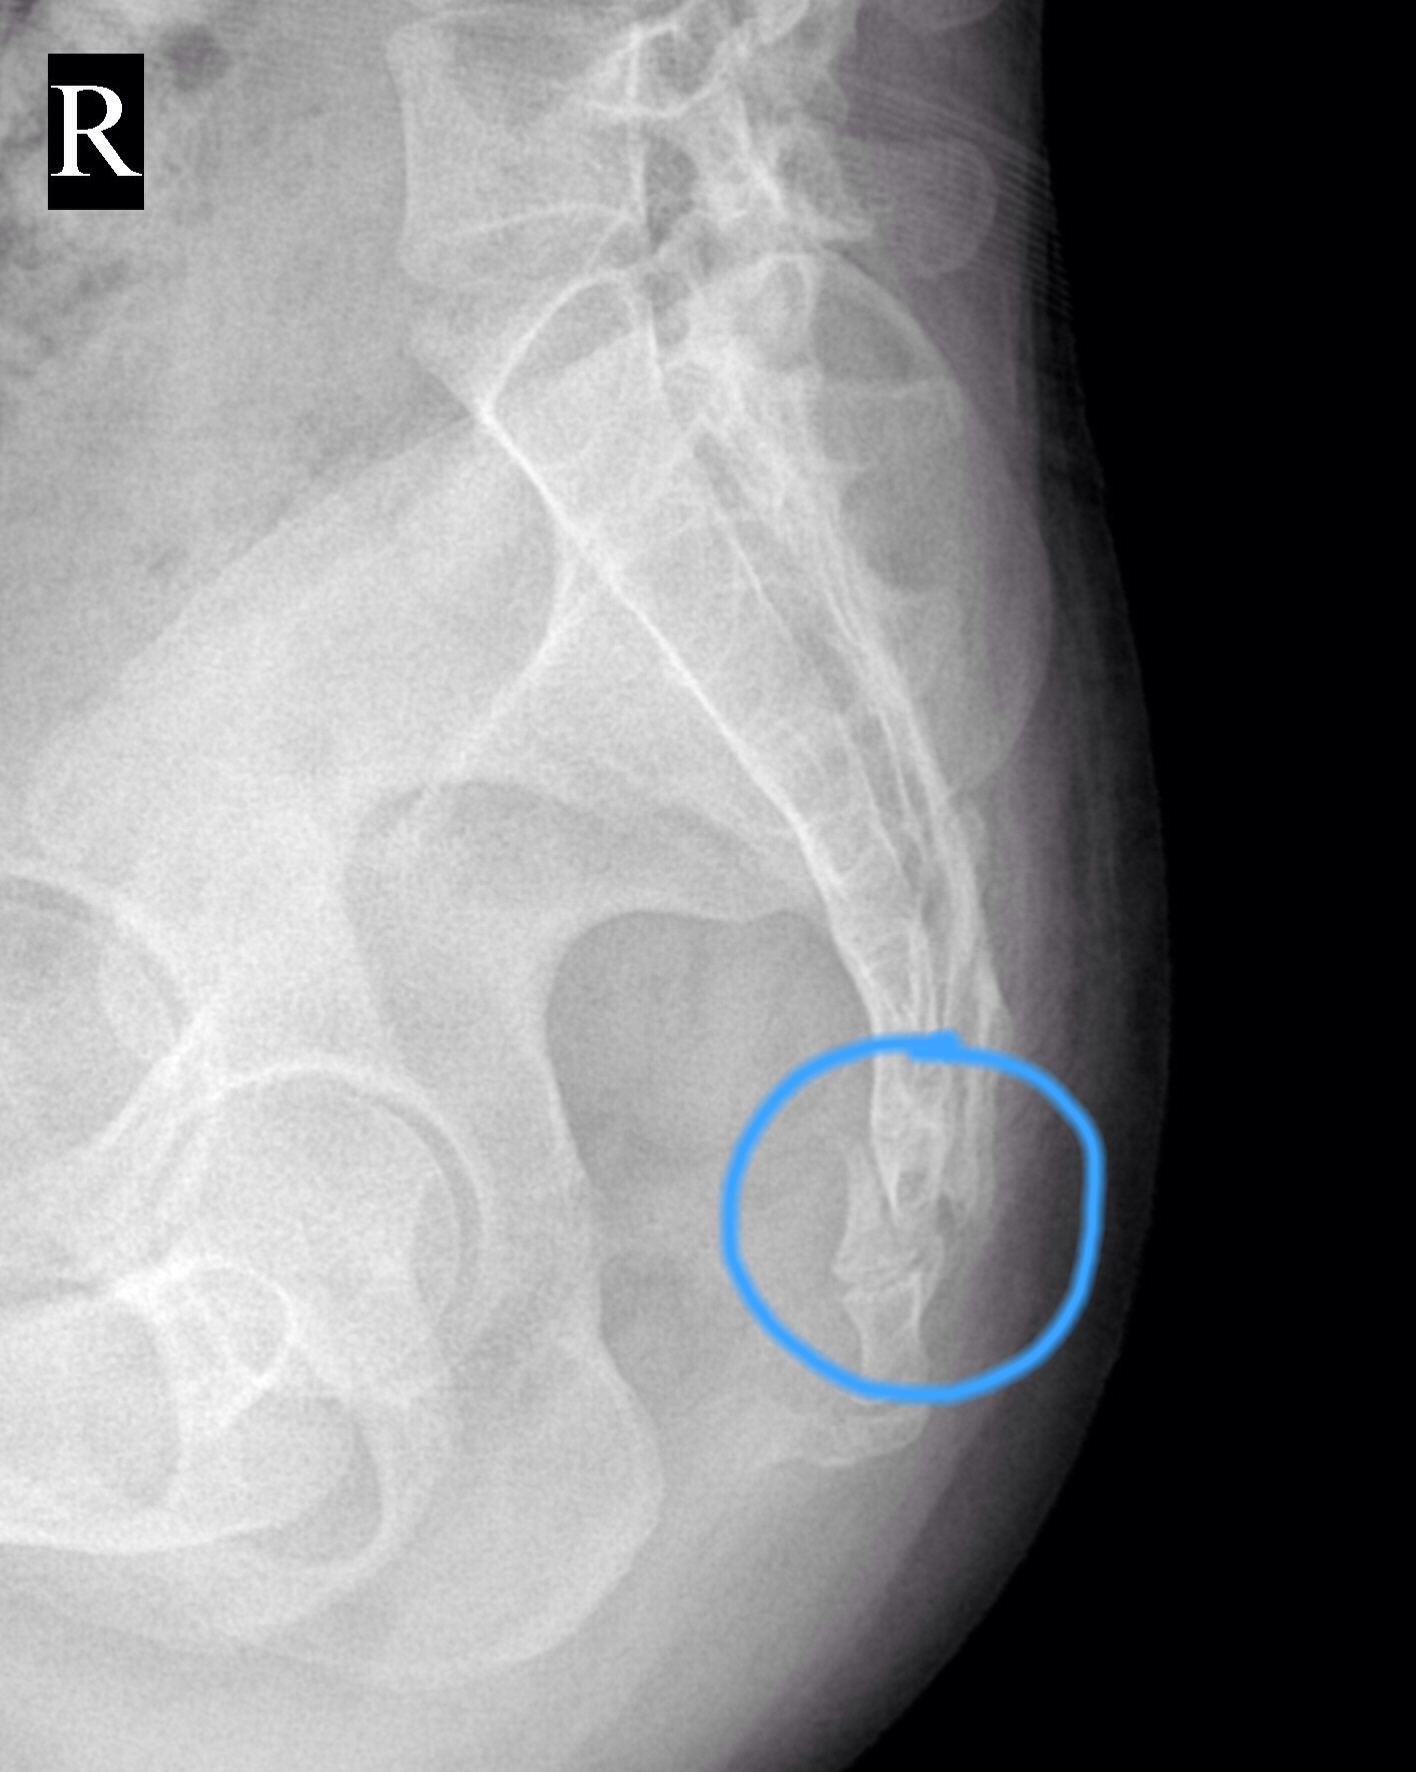

判断尾巴骨尾骨是否骨折,需结合外伤史症状表现及医学检查综合判断1 外伤史是重要线索尾骨骨折通常由直接外力导致,如滑倒时臀部着地从高处坠落或遭遇撞击若近期有此类明确外伤史,需高度警惕尾骨损伤的可能2 典型症状提示骨折风险尾骨骨折后,患者常出现以下症状腰骶部压痛与叩击痛轻。